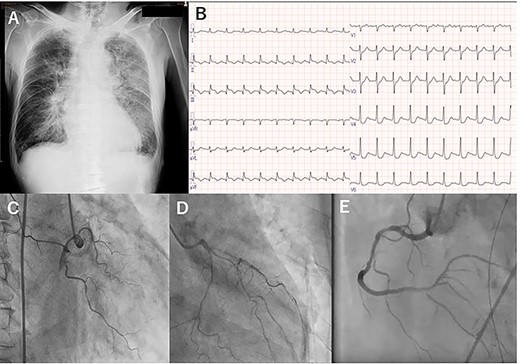

A few hours after treatment, his blood pressure collapsed despite the use of high-dose inotropic support and IABP. On cardiac auscultation, a holosystolic murmur had clearly developed at the left lower sternal border. Since transthoracic echocardiography showed VSP with a left-to-right shunt (Fig. 2A and B), VA-ECMO was started in the ICU and then the patient was transferred to the operating room (OR). Through the median sternotomy, cardiopulmonary bypass was established with aortic and bicaval cannulations, and cardiac arrest was induced with antegrade cold blood cardioplegia. The ventricular septum was approached through the right ventricle parallel to the right posterior descending artery. The VSP was repaired with an extended sandwich patch described by Asai et al. [2] Simultaneous coronary artery bypass grafting to the LAD was also performed using a vein graft. VA-ECMO was removed in the OR, and the IABP was removed on postoperative day (POD) 7. His CHF clearly improved (Fig. 2C), and he was extubated on POD 8.

Transesophageal echocardiography showed a defect with a left-to-right shunt (A). Ventricular septal perforation (VSP) (B). Postoperative chest X-ray (C).